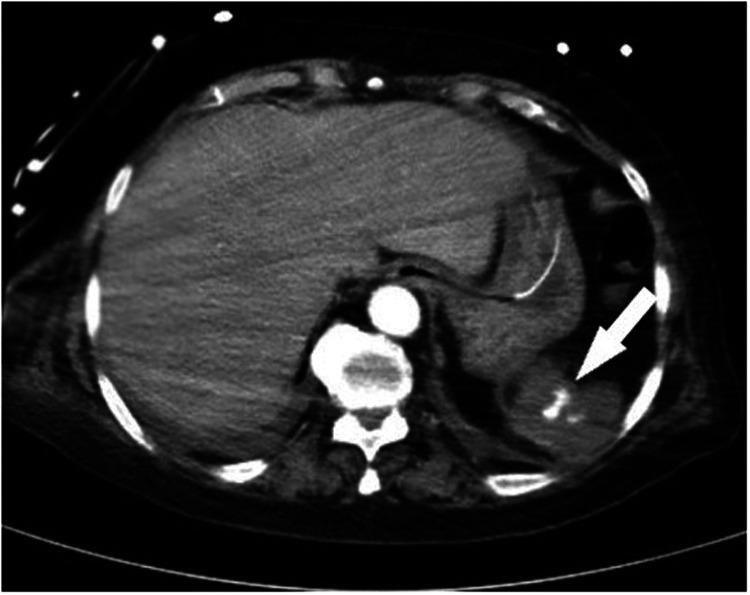

A 63-year-old woman was admitted to our hospital with herpes zoster viral infection and intermittent disorder of consciousness. On day 13 of hospitalization for glucocorticoid treatment, the patient experienced seven episodes of hematochezia. She had a 2-year history of systemic lupus erythematosus and had undergone splenectomy at 40 years of age. Computed tomography and electronic endoscopy revealed bleeding and contrast agent leakage into the splenic flexure of the colon. The patient underwent an emergency exploratory laparotomy and left hemicolectomy for suspected active hemorrhaging into the digestive tract. Pathological examination revealed that the bleeding had been caused by a fungal infection. No further hemorrhaging occurred after the surgery, suggesting that intestinal fungal infection might be a potential differential diagnosis for gastrointestinal bleeding in compromised hosts.

一名63岁女性因带状疱疹病毒感染和意识间歇性障碍入住我院。在住院第13天接受糖皮质激素治疗时,患者出现了7次便血。她有2年的系统性红斑狼疮病史,40岁时接受了脾切除术。计算机断层扫描和电子内窥镜检查显示结肠脾曲有出血和造影剂渗漏。患者因怀疑消化道有活动性出血接受了急诊剖腹探查术和左半结肠切除术。病理检查显示出血是由真菌感染引起的。术后未再发生出血,提示肠道真菌感染可能是免疫功能低下宿主胃肠道出血的一个潜在鉴别诊断。